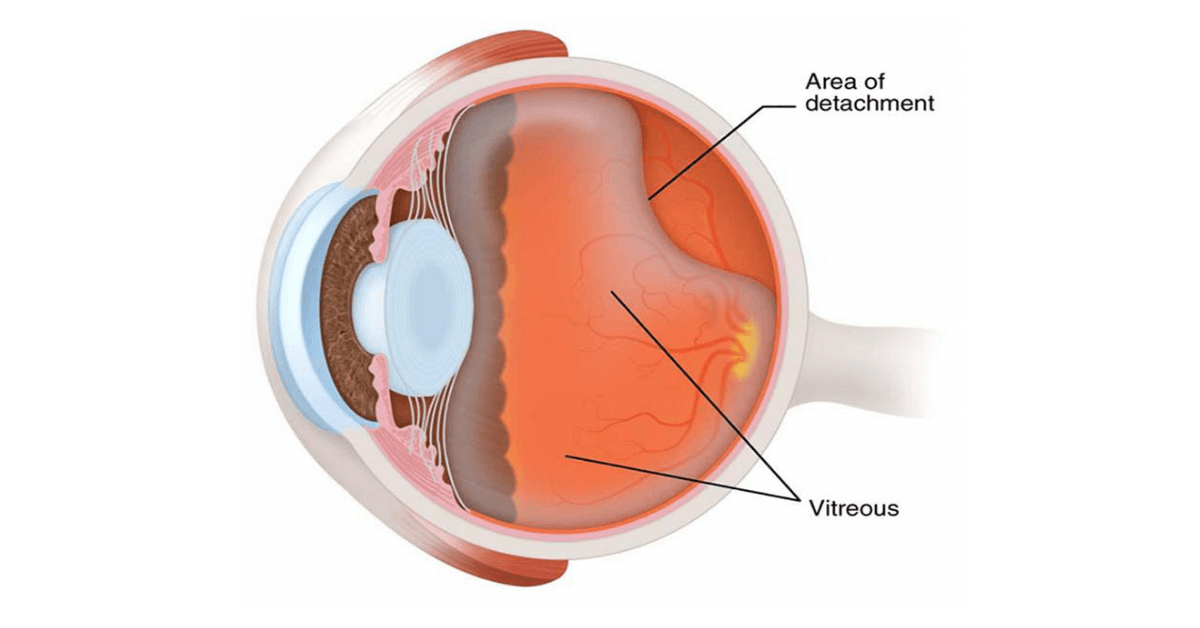

Изображения и анатомия сетчатки глаза